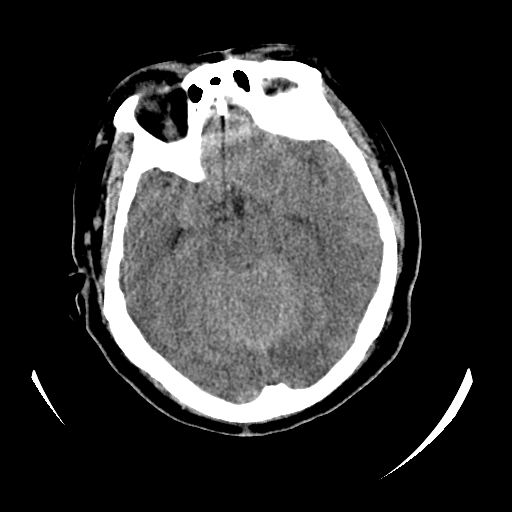

女,53岁,发现昏迷1天,血压不高,有精神病史。临床诊断:脑梗死?

ct诊断:1、双侧基底节区对称性脑梗塞。

2、双侧额叶、枕叶广泛密度减低,考虑缺血梗塞可能性大。

3、脑池小,脑沟浅,提示颅内高压。

测左枕叶白质ct值 约22hu 。请各位老师给出恬当诊断。

征象:病变呈对称性分布于双侧大脑半球,累及范围广泛,白质较灰质密度减低更为明显;脑沟变浅,脑池变窄;